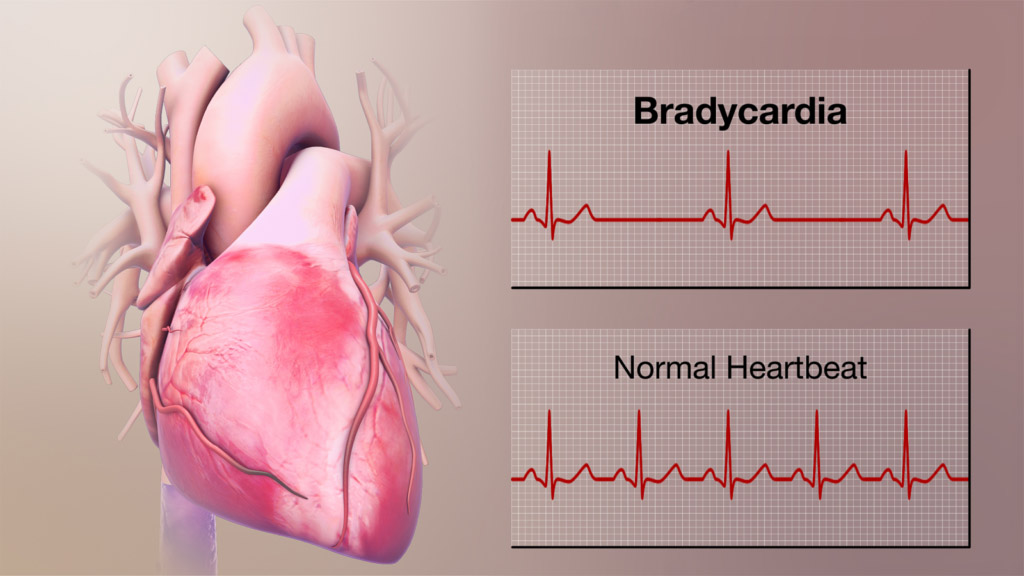

قیمت: 48٬000 تومان - دسته بندی فایل: پاورپوینتآریتمی های قلبی (ppt) 36 اسلاید کامل

فروش ویژه پاور پوینت حرفه ای آریتمی های قلبی با تخفیف استثنایی- نوع فایل : powerpoint (..ppt) ( قابل ویرایش و آماده پرینت ) تعداد اسلاید : 36 اسلاید